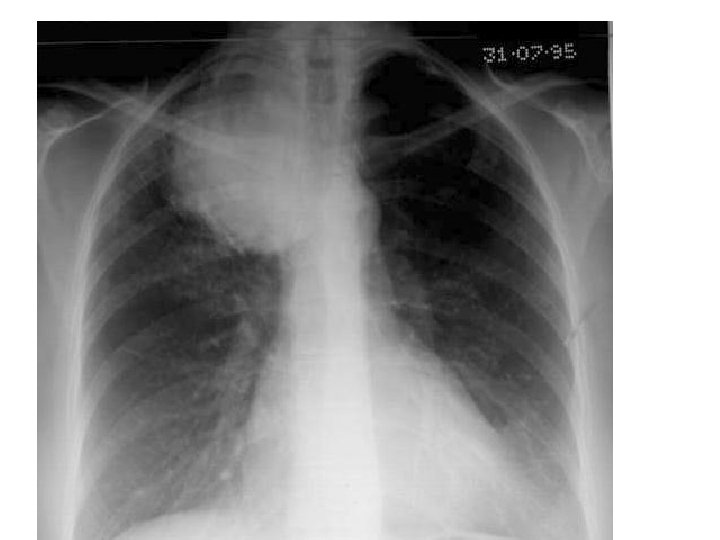

EXAMINATION OF THE CHEST Inspection § A-P diameter --pectus excavatum---funnel chest --pectus carinatum---pigeon chest § kyphoscoliosis § respiratory movements---resp. rate-{14 -18/min} i: e –hyperventillation—DKA, PE ---hypoventillation—type 2 resp. failure

v. SHAPE OF THE CHEST v. Pectus excavetum v. Pectus carinatum DILATED VEINS v. SVC obstruction---Ca lung